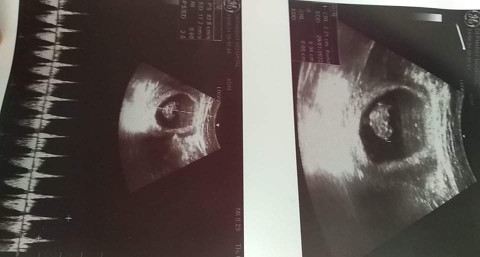

Post reply image